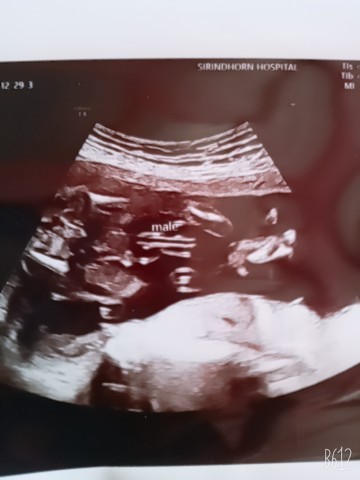

22+3ค่ะ